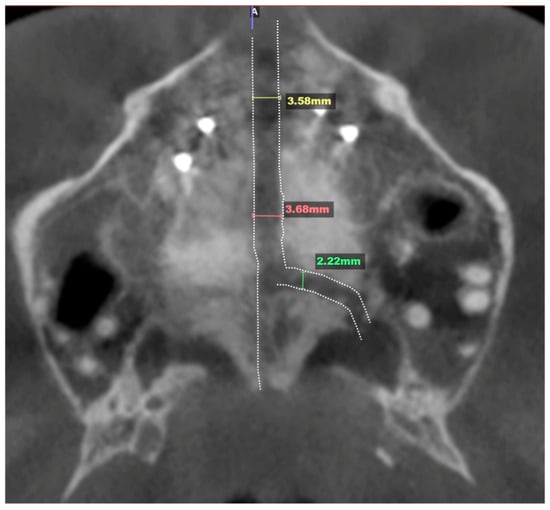

2.3.4. Postoperative Assessment, Outcome Analysis, and Asymmetry Correction